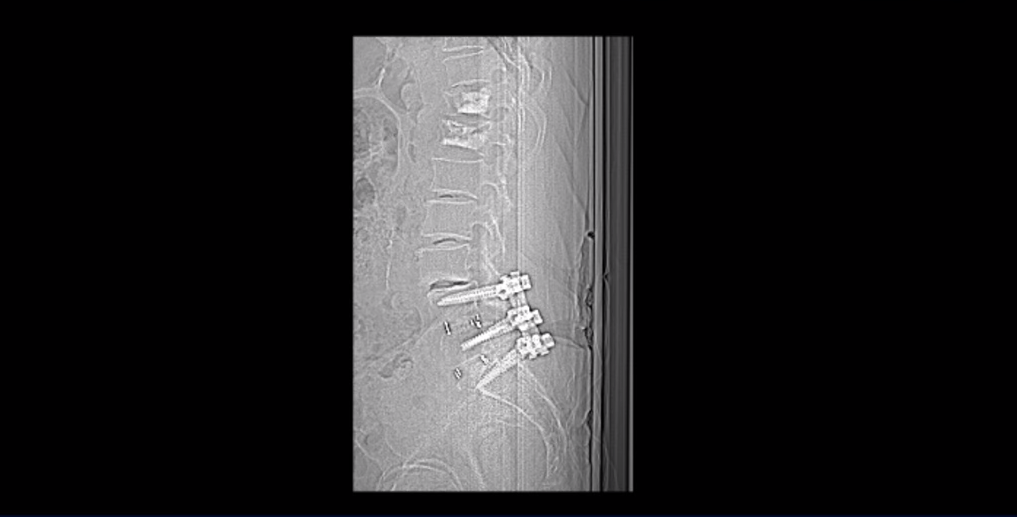

협착증 수술을 했는데, 특히 나사 박는 유합술까지 했는데도 게다가 수술이 잘 됐다는데도 수술 후 계속 엉덩이와 다리가 아프다는 환자분들이 많습니다. 협착증 수술은 엉덩이와 다리로 가는 신경이 눌려서 아프니까 그 신경 눌림을 수술로 풀어주는 것입니다. 그런데 신경 눌림을 시원하게 제대로 잘 풀어주기 위해 이 환자분처럼 여러 마디에 나사까지 박아서 하는 걸 유합술이라고 합니다.

그런데 수술은 신경 눌림만 풀어주지, 근육 문제는 해결해 주지 못합니다. 그래서 협착증 수술이 잘 됐더라도 근육 문제로 아픈 분들이 많습니다. 수술은 잘 됐다는데도 계속 허리, 엉덩이, 다리가 아픈 환자들은 아픈 쪽 근육들을 직접적으로 치료해서 근육 문제를 해결해 줄 필요가 있습니다. 이 환자분은 척추유합술 이후에도 지속되는 엉덩이와 다리 통증이 있었습니다. 그래서 이런 통증을 치료하기 위해 입원해서 근육 재활치료 받으셨습니다.